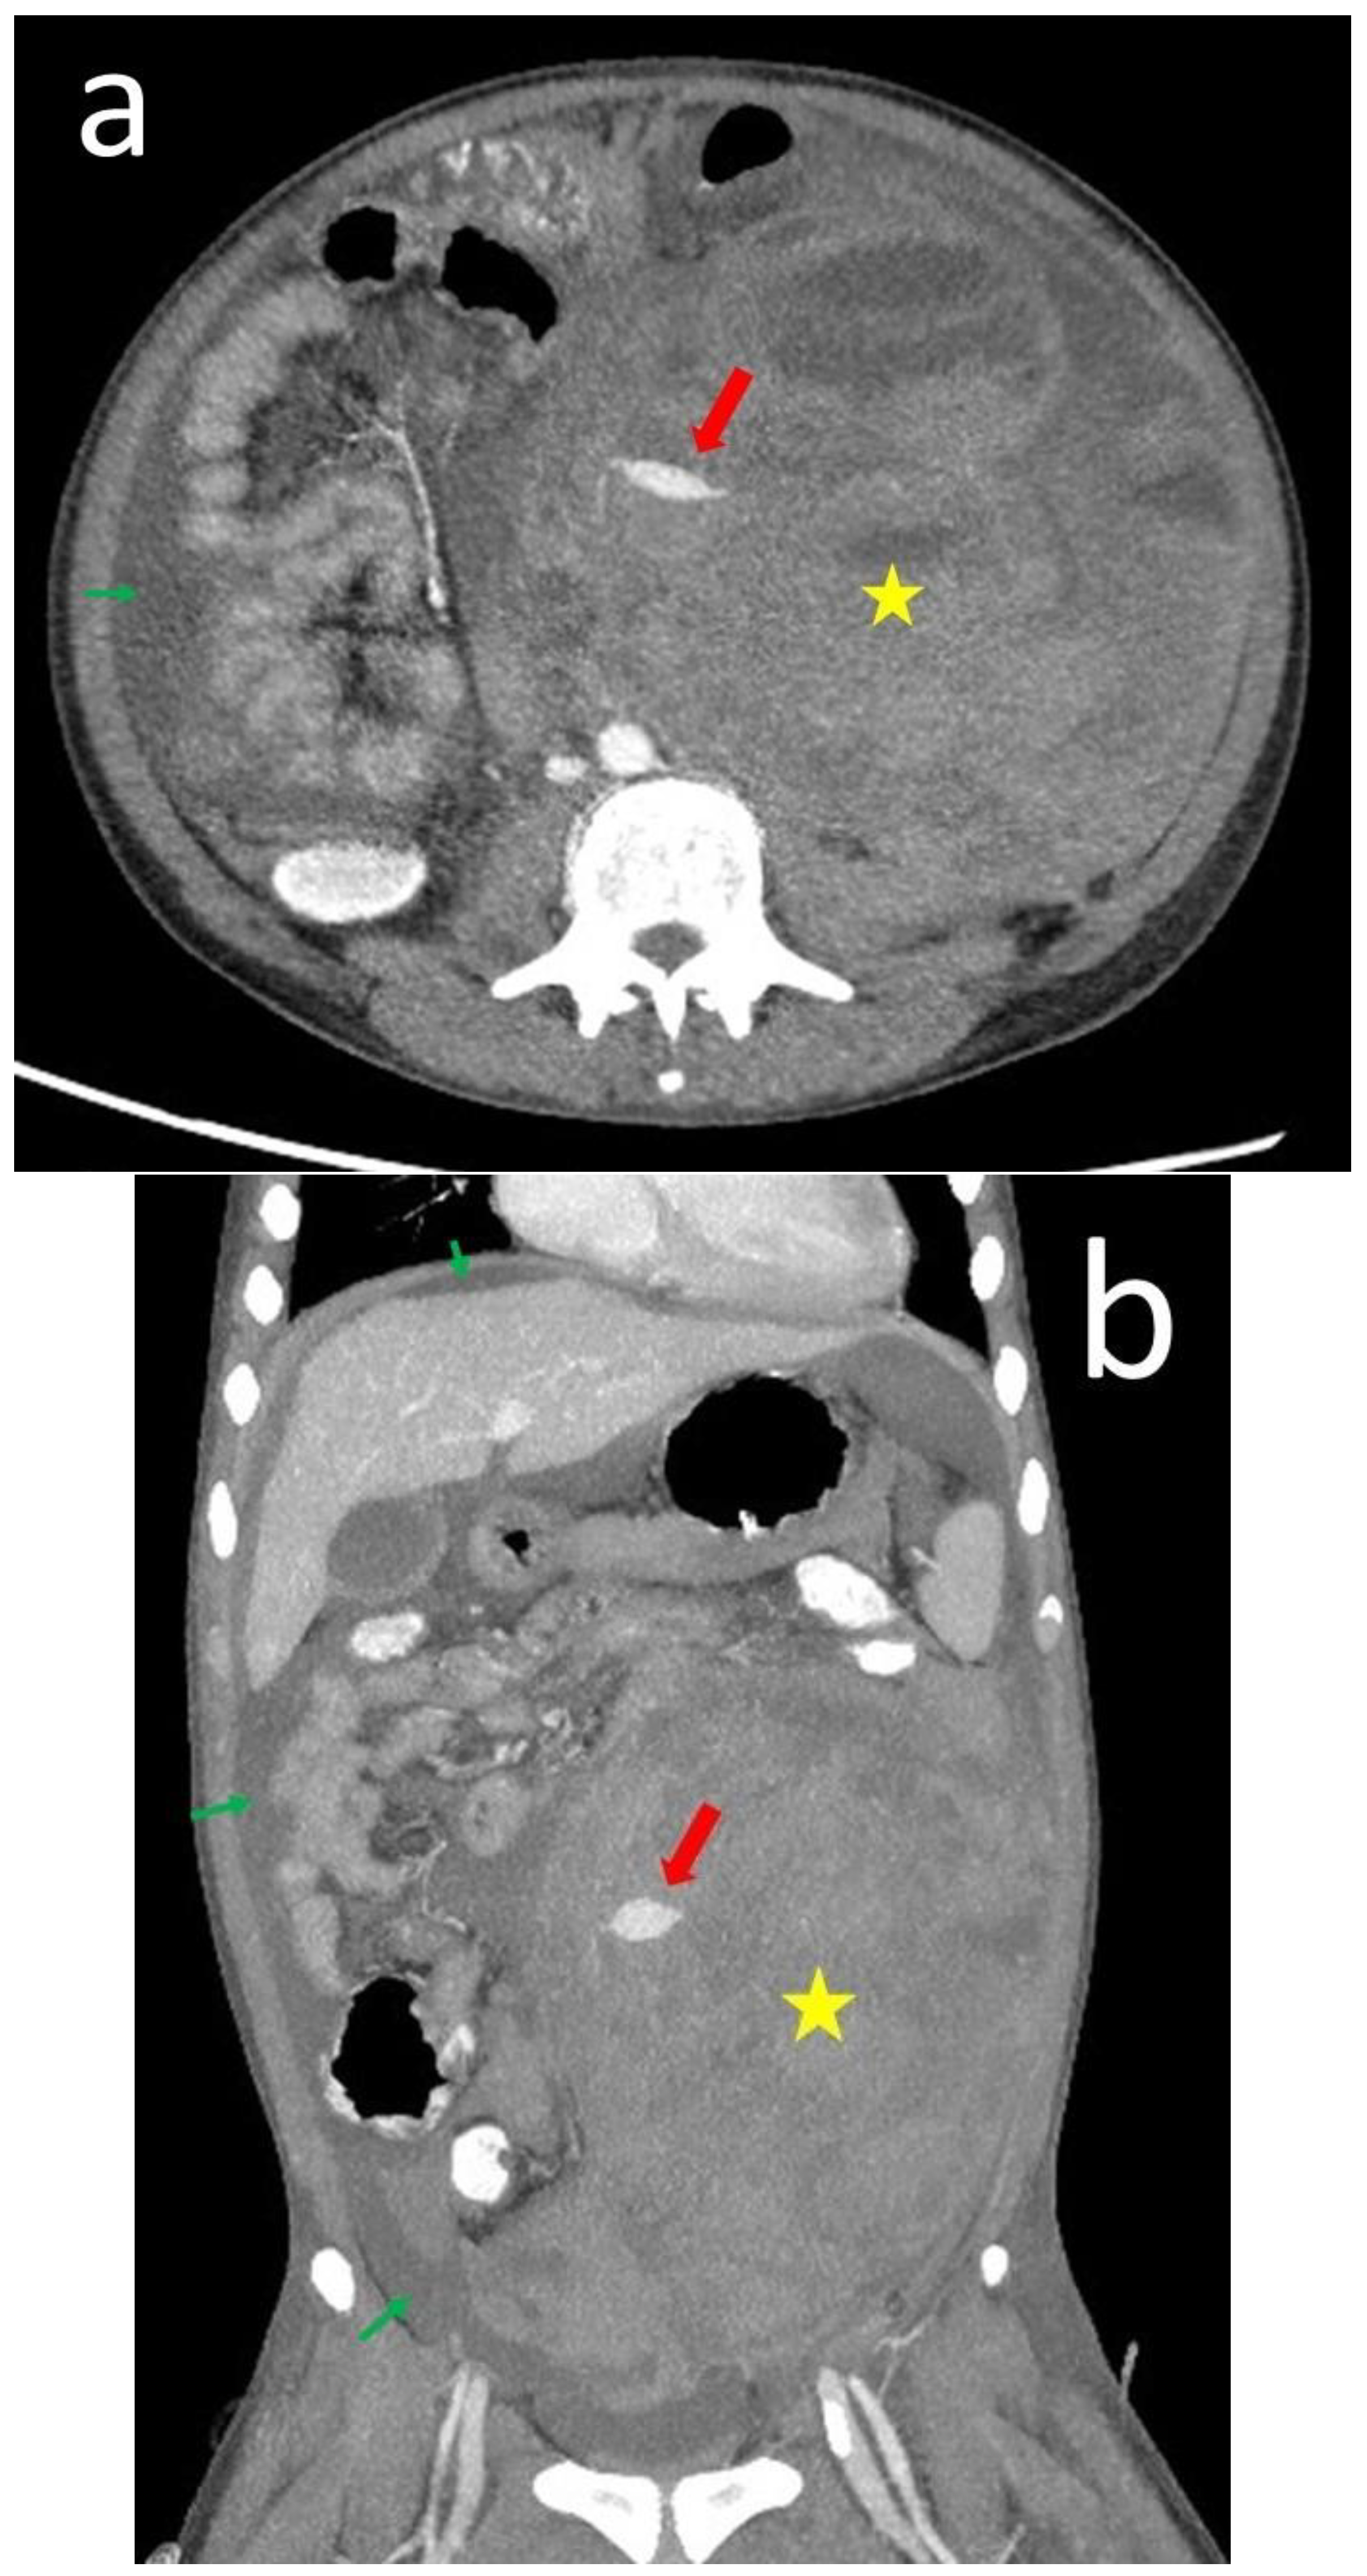

| 13 | Our case | 18 | Male | 12 | Flank pain Anemia(Hb: 6.7 g/dL) | Normal | Normal | CT | Angiodysplasia of the left renal artery & branch of IMA | N/A | Anti-dsDNA antibody Lupus anti-coagulant Anti-cardiolipin IgM | Embolization Steroid | N/A | Alive |